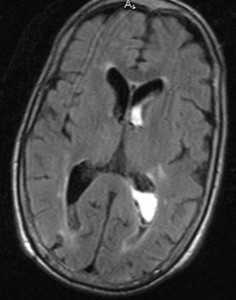

![Субдуральная гематома подострая]()

МРТ головного мозга. Аксиальная Т2-взвешенная МРТ. Подострая субдуральная гематома.

Субдуральная гематома обычно возникает вследствие разрыва вен. Причины субдуральной гематомы - травма, антикоагулянтная терапия, резкая декомпрессия при шунтировании желудочков по поводу гидроцефалии. Очень редко встречаются субдуральные гематомы при разрыве аневризм и АВМ. Клинические проявления связаны смасс-эффектом. Частота субдуральных гематом составляет около 1 случая на 10 тысяч населения. Располагаются субдуральные гематомы по конвекситальной поверхности, изредка, вдоль межполушарной щели и намёта, в области задней черепной ямки. Может быть сочетание субдуральной гематомы с кровоизлиянием в соседние участки мозга. прогноз в этих случаях неблагоприятный. Отображение гематомы на КТ и МРТ зависит от их давности. Субдуральные гематомы имеют форму серпа.